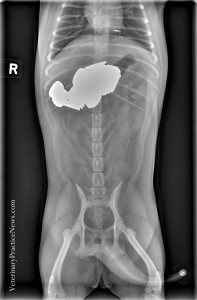

而每年都會舉辦的They Ate What X光大賽,至今已舉辦了9年,2014年的冠軍是一隻吞下超過30塊石頭的寵物蛙,第二名是吞下烤肉串的波音獵犬,第三名則是住在波特蘭的大丹,X光片發現有大量異物,手術後取出居然是43隻加半隻襪子而一名成名,只是主人一下子不見了43隻襪子,難道不曾懷疑是狗兒闖的禍嗎?看到照片中那排成一整排的襪子,真的要它們被拉出來實在太困難了啦~好在經過手術隔天,大丹順利返家休息,開始下一個奇幻冒險旅程?